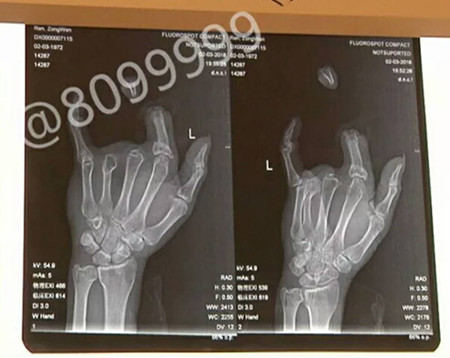

据了解,事发后,任师傅的妻子急忙收好丈夫的断指,又租了辆车把丈夫送到了昆明。在云南骨科医院,经过两个多小时手术,任师傅的断指被成功接好。目前手指循环良好,已经完全存活。

对于任师傅手指被缰绳勒断的原因,云南骨科医院手足显微外科王医生解释道:因为绳子受力面比较小,骡子力气比较大,这样就造成手指被勒在里面,用力一拉,手指的血管筋就全部被拉断。

在医生的介绍中得知,几年前任师傅在操作铡草机时,中指和无名指也曾被绞断,由于当时骨头碎裂的比较严重,无法进行再植。不过,这一次,他在受伤后第一时间来到医院,并且家人较好的保存的断指,给再植成功创造了条件。这也可以让他的左手具备一些劳动能力,不至于留下残疾。